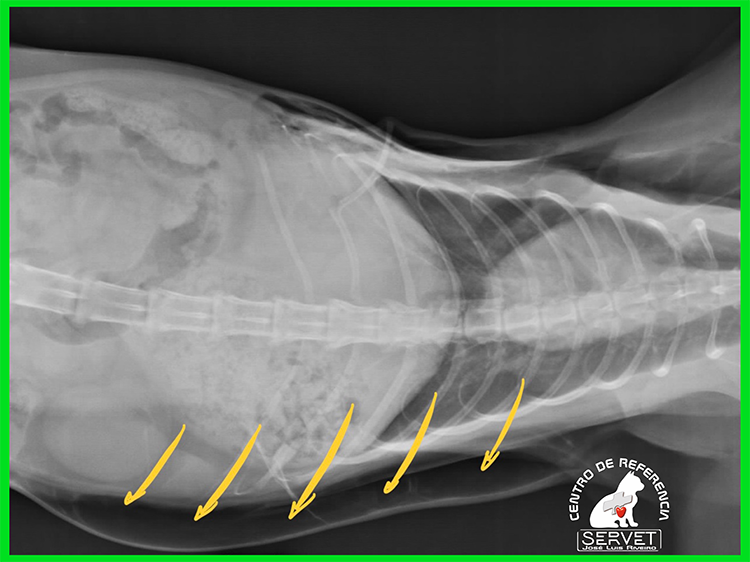

En la imagen superior puede verse el aire acumulado inmediatamente por debajo de la piel (flechas amarillas). En la foto puede verse al animal inmediatamente después de la cirugía de reparación del pulmón y la pared costal.